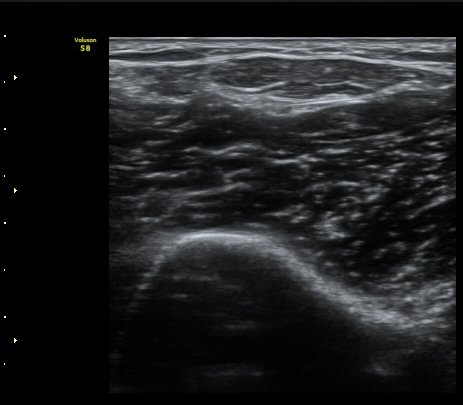

À̵ιڱ٠ÈûÁÙ Á¾´Ü¸é°Ë»ç¿¡¼­ ÈûÁÙÀÌ Àú¿¡ÄÚ°í °üÂûµÇ°í ÈûÁÙ ÁÖº¯ÀÇ ¼ö¾×Àú·ù°¡

¾Ö¸ÅÇÏ°Ô °üÂûµÈ´Ù(±×¸² 7). ŽÃËÀÚ ±ÙÀ§ºÎ¸¦ ÇǺÎÂÊÀ¸·Î ´©¸£´Ï ÈûÁÙÀÌ °í¿¡ÄÚ·Î

°üÂûµÇ°í ¼ö¾×Àú·ùµµ ¶Ñ·ÈÇÏ´Ù(±×¸² 8).